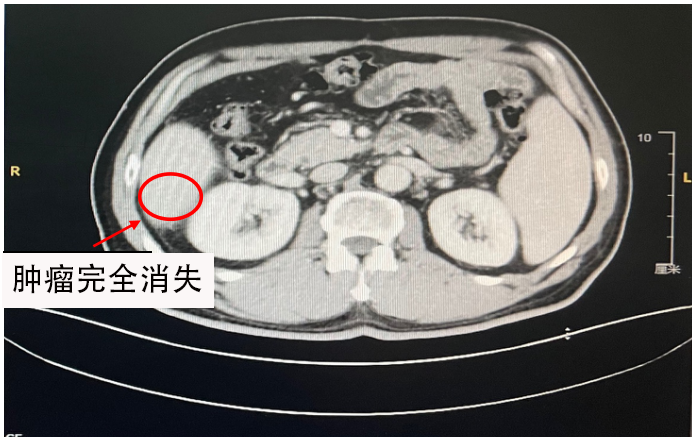

2024年1月15日再次复查腹部CT,提示靶病灶完全消失,疗效评估cCR临床完全缓解;

治疗前后的影像学评估(左上左中(2023-9-22腹部CT)、右上右中(2023-11-23腹部CT)

图片

(2024-1-15 腹部CT )

总体疗效评估:影像学确认的CR(RECIST v1.1),该患者仍在继续治疗中。